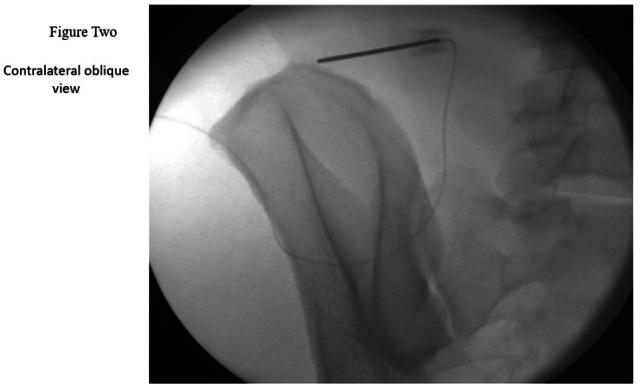

This case series aims to evaluate the effectiveness of the Micro Lead - SPRINT Peripheral Nerve Stimulation (PNS) System, (Cleveland, Ohio, USA) for treating cluneal neuralgia, utilizing both fluoroscopic and ultrasound guidance for accurate nerve localization.

A retrospective review was conducted on six nonconsecutive patients who underwent Micro Lead - SPRINT Peripheral Nerve Stimulation (PNS) System, (Cleveland, Ohio, USA) implantation for cluneal nerve entrapment at MetroHealth System between August 2021 and January 2024. Patient selection focused on individuals with cluneal neuralgia refractory to conservative treatments. Data collection included demographics, pain characteristics, opioid usage, and follow-up evaluations at 30, 60, 90 days, and 2 years post-procedure. Outcomes were assessed using the Numerical Rating Scale (NRS) for pain. Dividing the NRS score by the maximum score (10) and multiplying by 100 expresses pain intensity as a percentage.